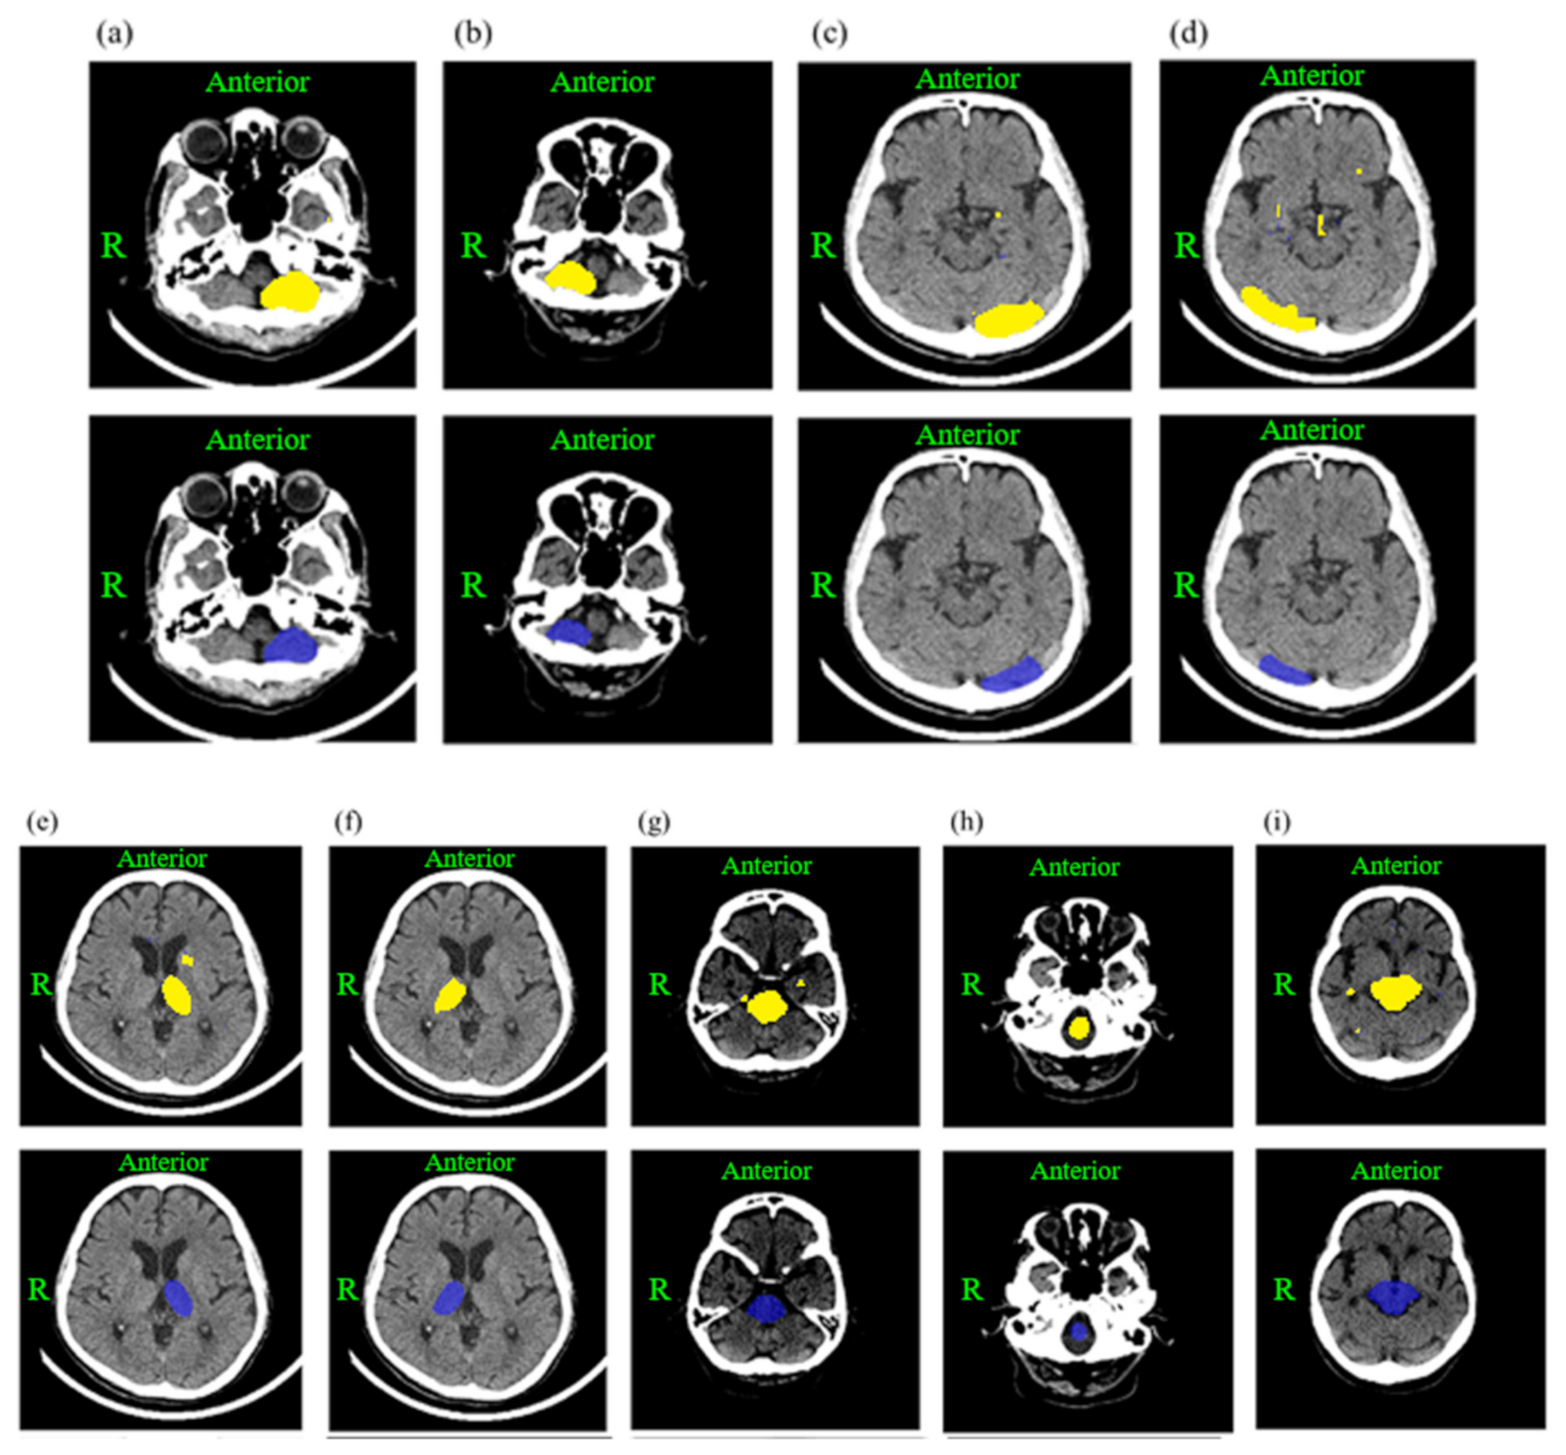

2.3. Deep Learning Model Development and Training

| Structure | Mean IoU | Subset I IoU | Subset II IoU | Subset III IoU | Subset IV IoU | Subset V IoU |

|---|---|---|---|---|---|---|

| Left lateral cerebellum | 0.78 | 0.77 | 0.81 | 0.79 | 0.75 | 0.78 |

| Right lateral cerebellum | 0.79 | 0.78 | 0.83 | 0.81 | 0.77 | 0.76 |

| Left lateral occipital lobe | 0.74 | 0.78 | 0.73 | 0.77 | 0.75 | 0.67 |

| Right lateral occipital lobe | 0.68 | 0.66 | 0.74 | 0.72 | 0.63 | 0.65 |

| Left lateral thalamus | 0.73 | 0.72 | 0.68 | 0.76 | 0.79 | 0.70 |

| Right lateral thalamus | 0.75 | 0.73 | 0.78 | 0.79 | 0.71 | 0.74 |

| Medulla oblongata | 0.82 | 0.85 | 0.82 | 0.84 | 0.81 | 0.78 |

| Midbrain | 0.83 | 0.82 | 0.80 | 0.86 | 0.85 | 0.82 |

| Pons | 0.75 | 0.74 | 0.77 | 0.79 | 0.72 | 0.73 |